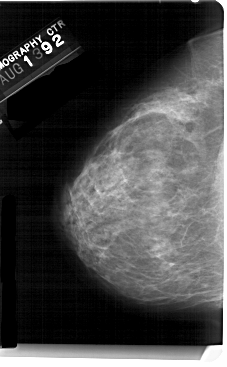

A_1434_1.RIGHT_MLO

RIGHT_MLO LINES 5491 PIXELS_PER_LINE 3376 BITS_PER_PIXEL 12 RESOLUTION 43.5 OVERLAY

FILE: A_1434_1.RIGHT_MLO.OVERLAY

TOTAL_ABNORMALITIES 1

ABNORMALITY 1

LESION_TYPE MASS SHAPE OVAL MARGINS CIRCUMSCRIBED

ASSESSMENT 4

SUBTLETY 4

PATHOLOGY BENIGN

TOTAL_OUTLINES 1

BOUNDARY